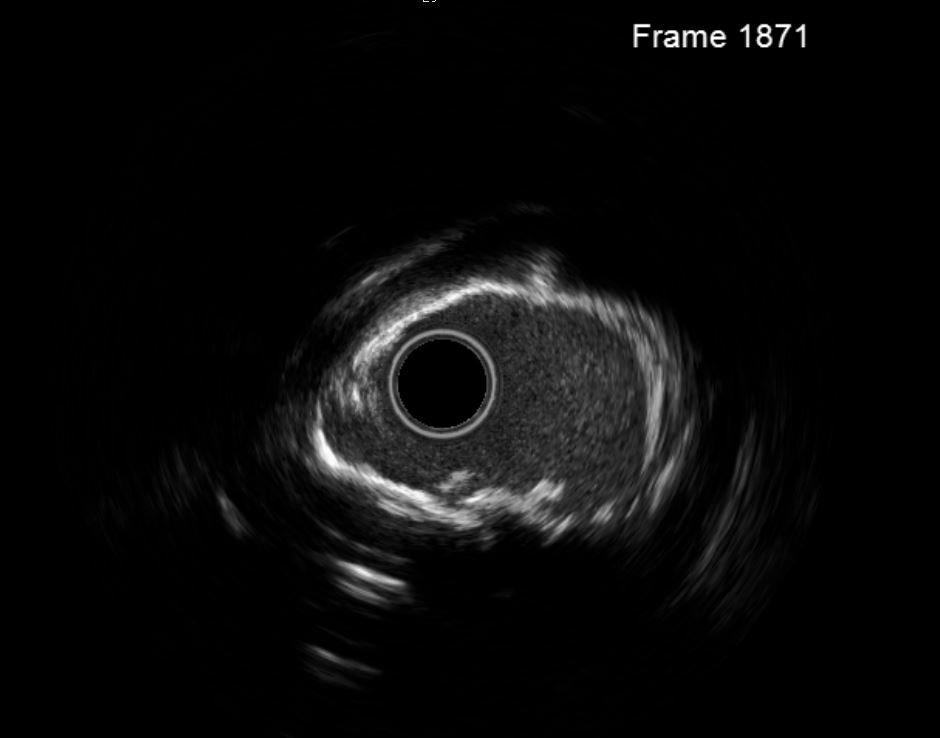

Given the balloon-uncrossable lesion, rotational atherectomy was considered necessary to facilitate stent delivery and proper expansion. However, the heavily calcified plaque was located at a curvature of the RCA, raising the risk of complications with multiple burr passes. In addition, the patient¡¯s cardiac and renal function was compromised, and even minor complications could have resulted in life-threatening consequences. Therefore, a combined strategy of rotational atherectomy and intravascular lithotripsy (IVL) was planned after thorough discussion.A temporary pacemaker was placed first as backup before initiating the procedure. The microcatheter could not cross the lesion, thus a direct wiring technique with a RotaWire was performed. Rotational atherectomy was carried out with a 1.25 mm burr at high speed (176,000–178,000 rpm). Episodes of bradycardia occurred but the lesion was successfully crossed. Intravascular ultrasound (IVUS) revealed severe calcification with 270¡Æ arc in the distal LAD and 360¡Æ in the mid LAD, with partial fracture. IVL was delivered to the distal RCA, followed by liquefaction of the calcium from d-RCA to m-RCA. Non-compliant balloon predilatation was then performed, and repeat IVUS confirmed multiple cracks with significant luminal gain. Two drug-eluting stents were deployed according to measurement from IVUS. After adequate post-dilatation, IVUS confirmed optimal stent expansion with good apposition and no edge dissection.